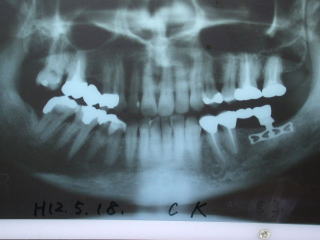

●インプラントのレントゲン写真例

上の奥歯の例です。

上は上顎洞という骨空洞があり、インプラントの植立が困難な場合が多いです。

こちらのケースは左上の保険外延長ブリッジのロウ着部分が破損のためインプラントを入れて3歯連続冠にしました。